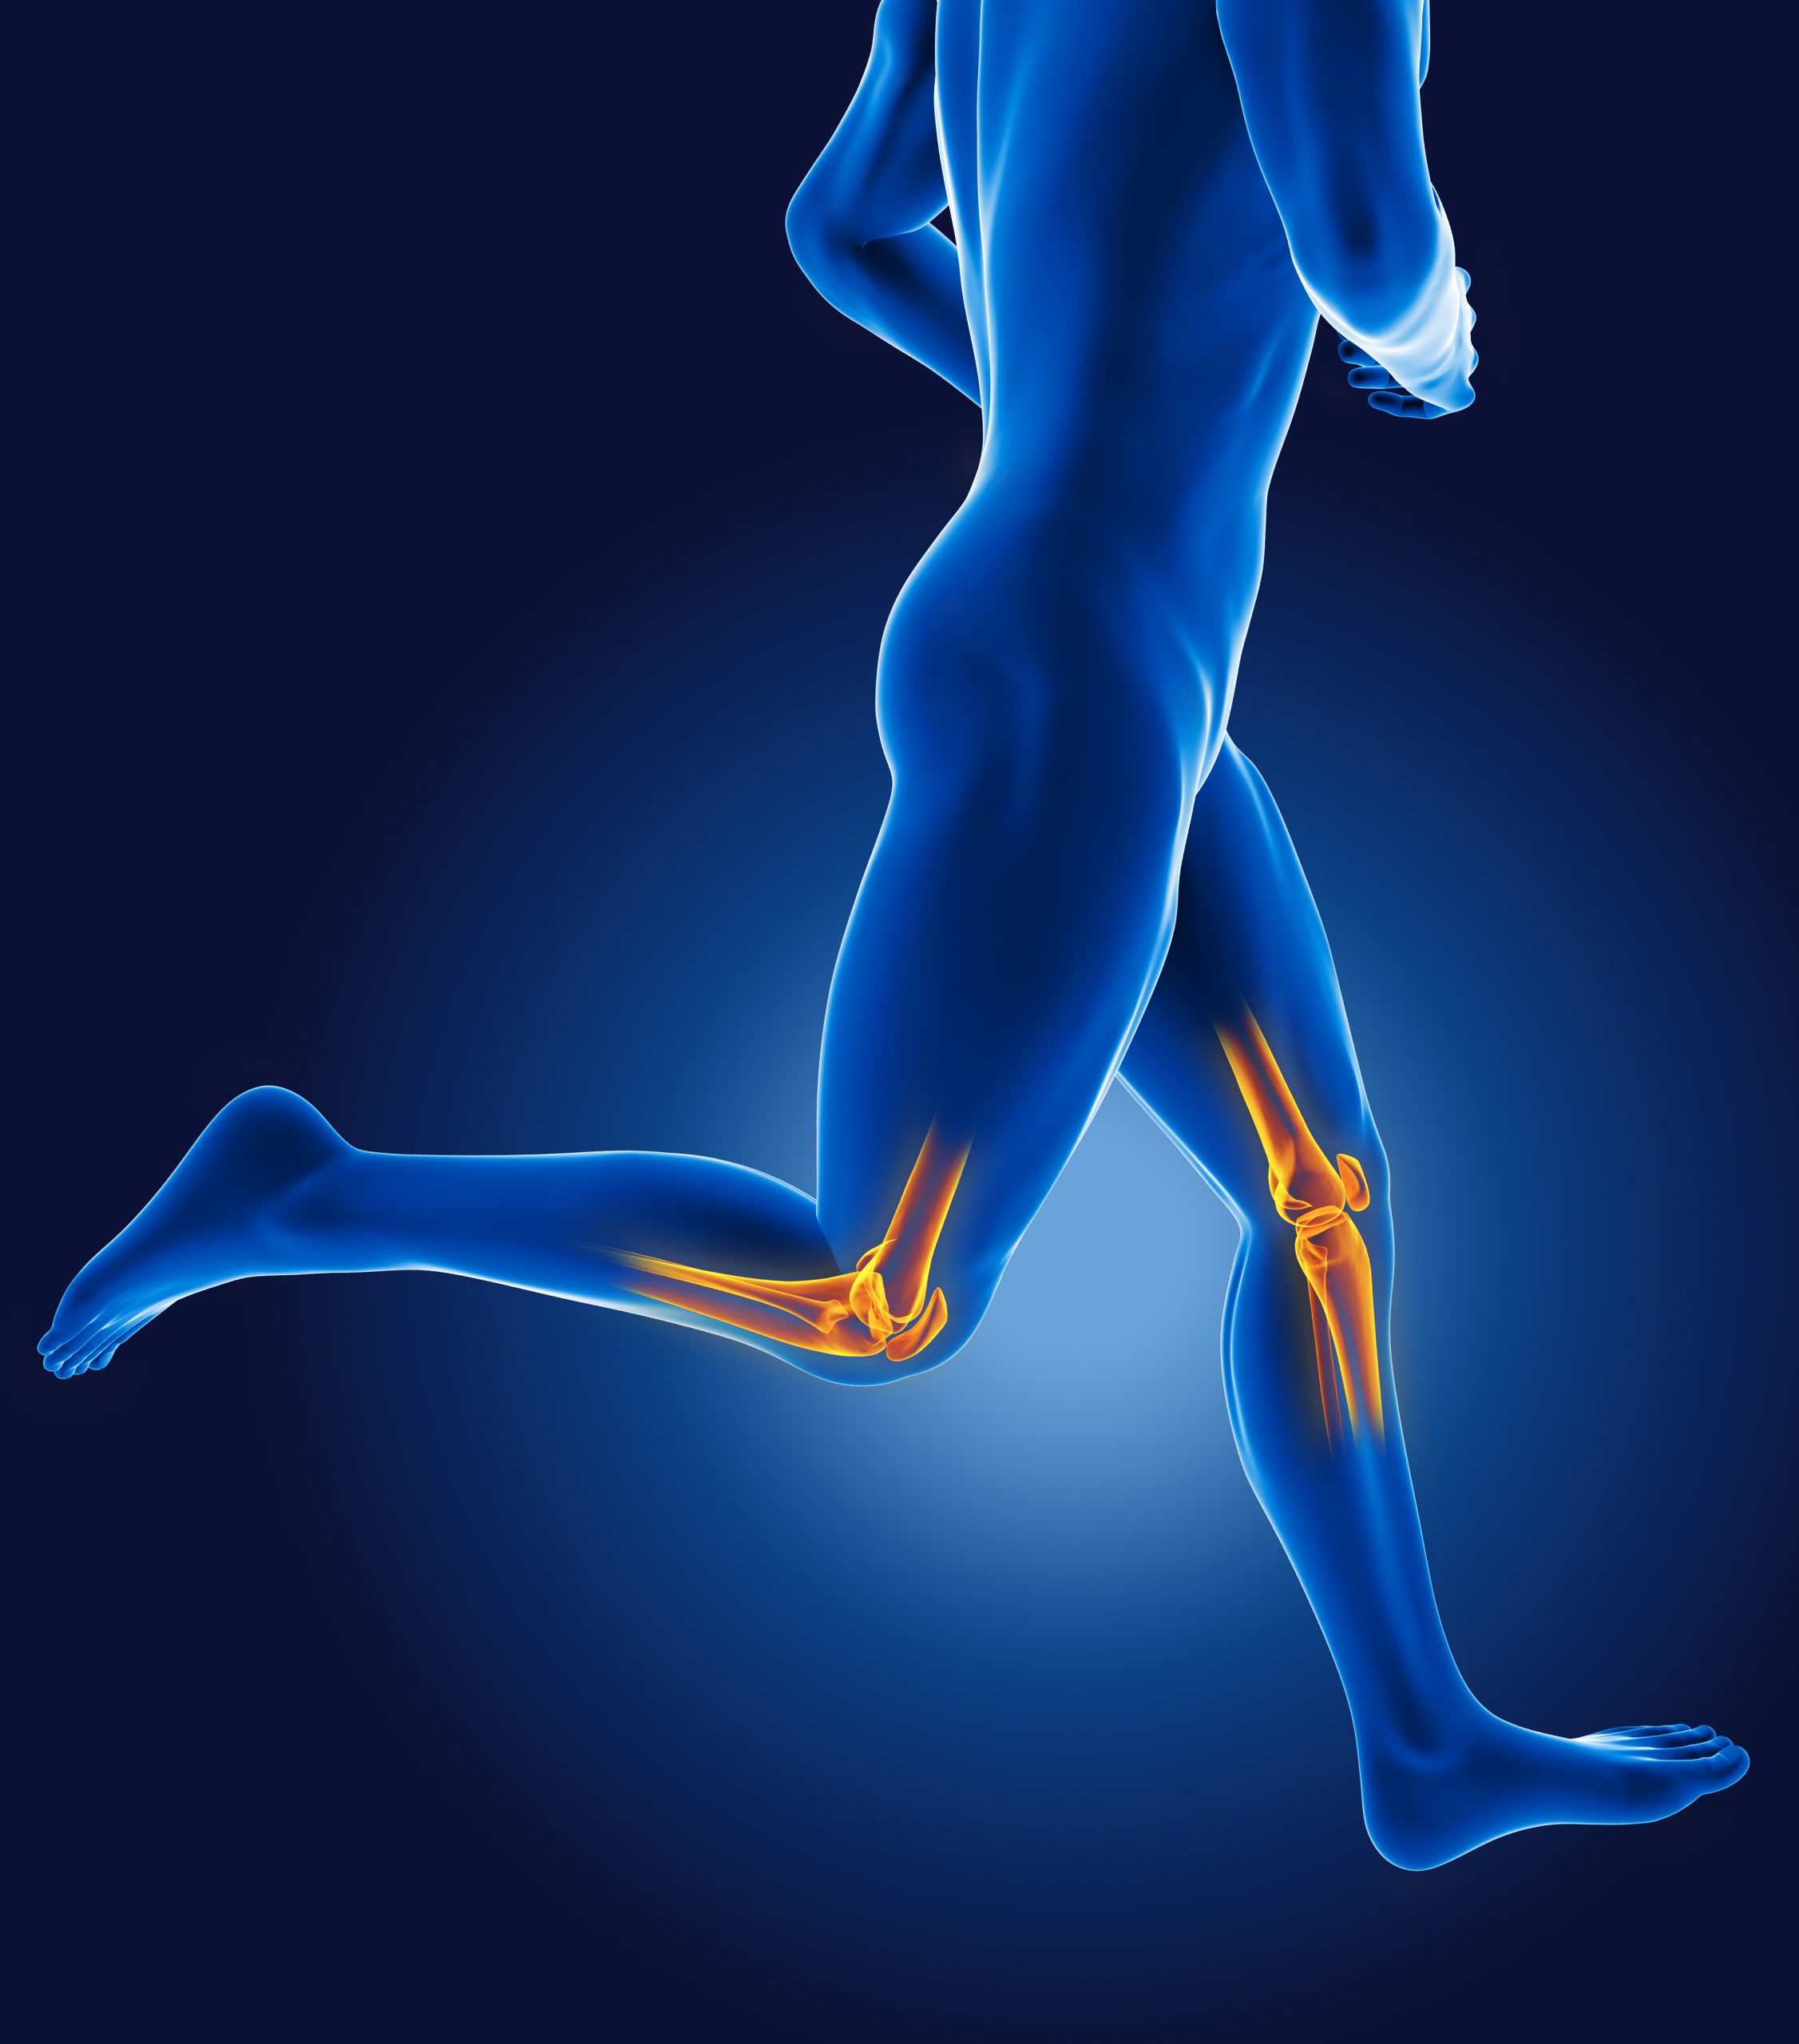

Knee Pain is one of the most common sources of pain for people. Although knee pain can be attributed to underlying diseases, it can also occur due to injuries, sitting in a constrained area, lack of use, and heavy physical activity.

Symptoms of knee pain include redness and warmth to the touch, weakness or instability, swelling and stiffness, popping or crunching sounds, and inability to fully straighten the knee. You will want to seek medical attention if you are unable to fully extend or flex your knee, see an obvious deformity in your leg or knee, have severe knee pain that is associated with an injury, or you have a fever, in addition to other symptoms related to knee pain.

Conditions that include knee pain as a symptom:

- Sprained knee

- ACL injury

- Osteoarthritis

- Patellofemoral pain syndrome

- Bursitis